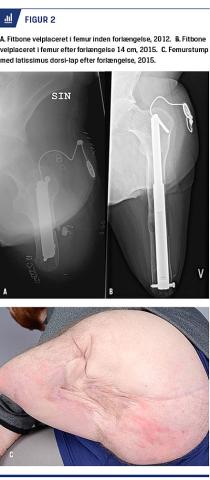

Trods et forløb over to år opnåedes der imidlertid ikke stabil gangfunktion, og en væsentlig del af døgnet måtte han tilbringe i kørestol. I samråd blev det derfor besluttet at forlænge venstre femur med et motoriseret marvsøm (Figur 2A). Behandlingen blev udført fra 2012 på Ortopædkirurgisk Afdeling på Aalborg Universitetshospital og forløb over fire år. Patienten blev kontrolleret med røntgenoptagelser, som viste heling med fin densitet af knoglen i takt med forlængelsen. LD-lappen fulgte med knoglens vækst og var vital under hele forløbet til en samlet forlængelse på 14 cm (Figur 2B + C).

Knogleforlængelsen blev udført med Fitbone, der er et intramedullært motoriseret søm. Brugen af Fitbone tillader modsat ekstern fiksering tidlig bevægelse af led, da sømmet ikke penetrerer og fikserer hud og muskler. Patienterne rapporterer om færre komplikationer under behandlingen, men ulempen er, at det kræver en ekstra operation at fjerne apparatet [3].